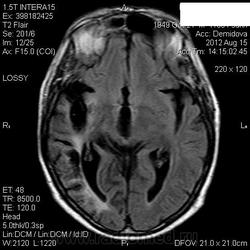

Мои собственные наблюдения.

1 случай -локальная гемиатрофия.2 случай-диффузная.

Молодой человек после автомобильной аварии.3 года лежит.Двигаются только глаза.Зрелище душещипательное.

Евгений, конечно же, мои случаи не являются "чистой" атрофией-согласна.Мне пока не встречались случаи болезни Пика, Альцгеймера и другие "чистой воды" атрофии.Второй случай- состояние после длительной комы вследствие автодорожной травмы 3 года назад.Пациент проходил исследование в прошлом году , в этом родители привезли на динамику.